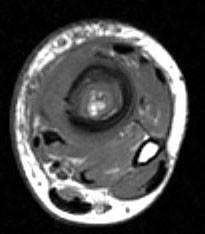

问题 男,33岁,有发热,小腿局部有疼痛,红肿并有压痛,请结合图像,选择最佳答案 ( )

选项 A、骨髓瘤 B、骨化性肌炎 C、脂肪瘤 D、未见异常 E、骨髓炎

答案 E